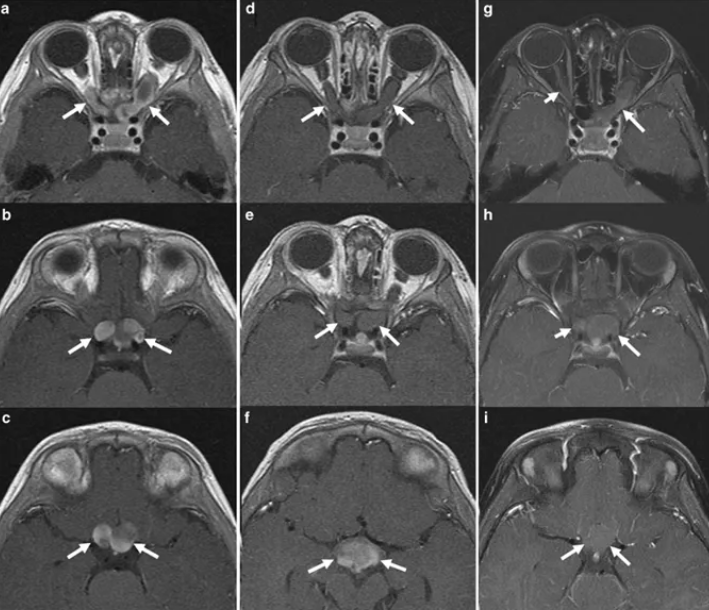

视神经胶质瘤会导致失明吗?INC国际神经外科专家指出,虽然视神经胶质瘤通常被归类为良性的低等级WHO(国际卫生组织)1级毛细胞星形细胞瘤,一般很少进展到高等级。但视神经胶质瘤由于生长在视神经上,随着缓慢的增大,会不断影响孩子的视力,较终可能导致失明。视神经型胶质瘤在临床上典型的表现为早期出现视力逐渐下降、视野缺损,随着病变体积增大,出现眼眶占位性病变的特点,即进行性眼球突出、眼球运动受限、斜视等,故视力下降先于眼球突出出现。在婴幼儿期的视神经胶质瘤多表现为眼球震颤和斜视。特别是儿童出现视力下降时因其主诉不明确,往往在出现明显的眼球突出或因视力丧失导致废用性斜视时被家长发现才就诊,故儿童患者就诊时视力损伤已很严重甚至失明。

视神经胶质瘤能治好呢,手术切除会导致失明吗?任何疾病,只要沾上一个瘤字,都不是容易治疗的,视神经胶质瘤也一样,即使国际卫生组织(WHO)将其归为I级良性肿瘤。对于进展性视神经胶质瘤的治疗可通过化疗、放射治疗或外科手术进行,一般手术切除是更佳的选择。但由于视神经胶质瘤位于颅内,周围血管环绕,布满重要神经组织,所以手术难度是高的,手术不仅难以取得高切除率,而且还可能导致孩子失明。但是想要使视神经胶质瘤预后更好的话,是需要确定一个手术高切除率的。手术切除率一般只要高于90%,再次复发的几率较低,但是要在不损伤周围神经组织及要保留患者视力的情况下,达到高切除率对医生是一个较大的挑战,考验医生的技术和其手术经验。这也是为什么国内的医院建议前文的小孩采取保守治疗。